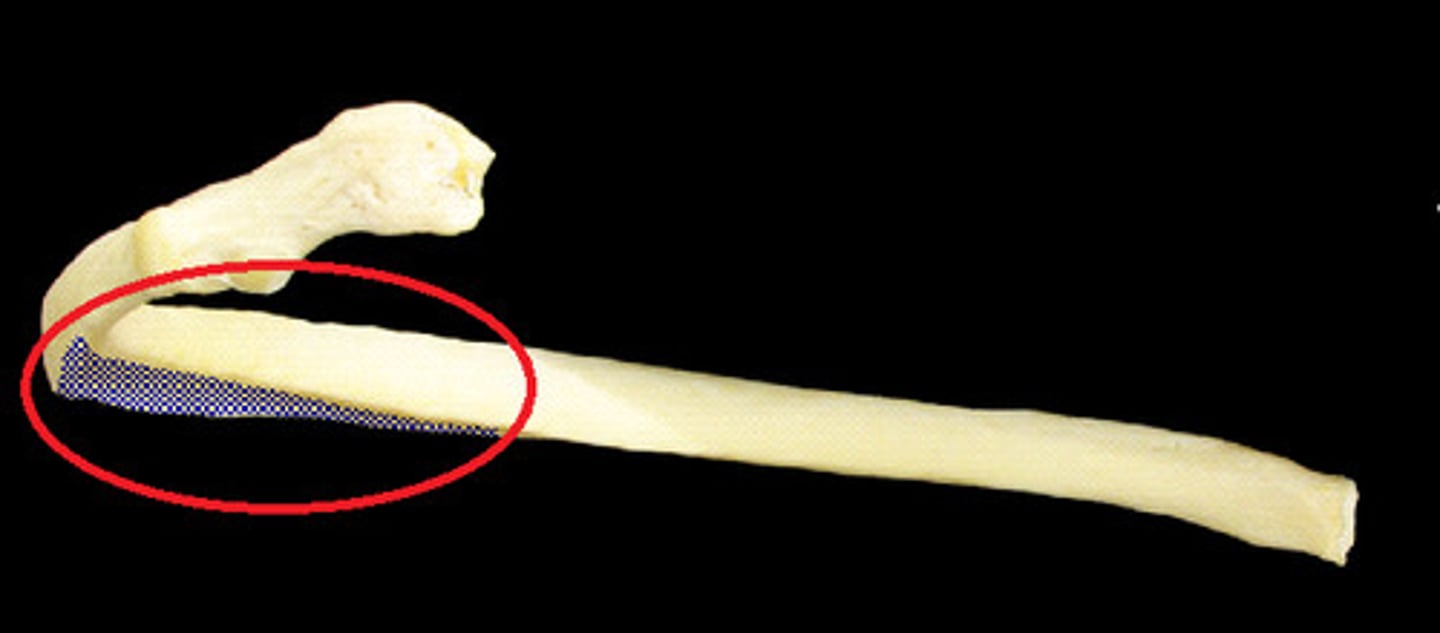

costal groove of rib

What is this structure?